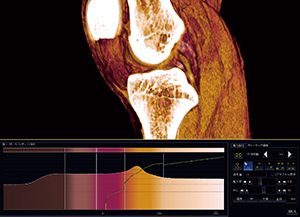

前十字靭帯不全断裂─術前および術後のCT

左膝前十字靭帯不全断裂の再建術を行った症例を紹介する。術前のCT検査はMPR画像と骨の3D画像が主な目的となり,術後のCT検査は骨孔の位置評価が主な目的となるが,本症例ではVR画像を用いて術前後の前十字靭帯の評価も行った(図4,5)。

術前のVR画像では,前十字靭帯の大腿骨付着側が菲薄し明瞭に描出されておらず,不全断裂の所見を示している。また,前十字靭帯断裂の間接所見として,脛骨の前方偏位や後十字靭帯のたわみも観察された。

術後では再建靭帯のCT値が周囲の軟部組織よりやや高く,靭帯自体が太いためVR画像で明瞭に描出できた。このようなVR画像が得られれば患者説明にも有用である。

術前のVR画像で断裂部が菲薄であったが,これに関してはWS上で表示ができていないのか,断裂を示す所見として表示されないのかを見極められるような画像を作成しなければならない。そのためには,靭帯の走行に対して最適な角度でカットし前後の情報も漏らさないことと,やはり画像ノイズの少ないデータを基にVR画像を作成し,オパシティカーブの調整で靭帯を明瞭に表現することが重要になる。

図4 左前十字靭帯再建術術前のVR画像と |

図5 左前十字靭帯再建術術後のVR画像と |